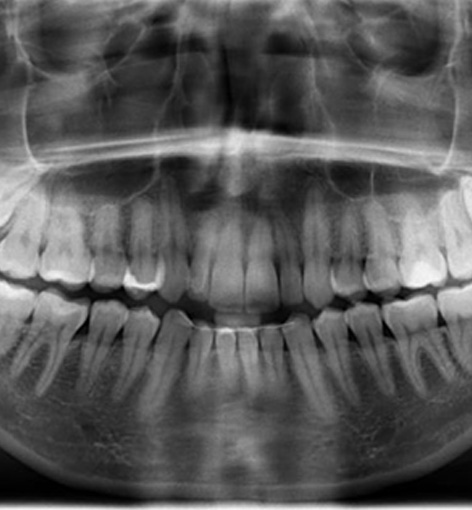

Wisdom teeth are the third set of molars, which develop at the back of the mouth. Typically, they come in when a person is in their late teens or early 20s. Our ancient human ancestors needed wisdom teeth to consume a rough diet. In modern times, however, these teeth are viewed as vestigial. In fact, many people’s mouths are too small to accommodate them.

Not everyone has to get their wisdom teeth removed. However, this procedure is often necessary because the third molars can cause significant oral health problems, especially if they are impacted (stuck beneath the gumline). For example, you may be at risk of:

The wisdom teeth might even push against nearby teeth, causing them to shift out of place.